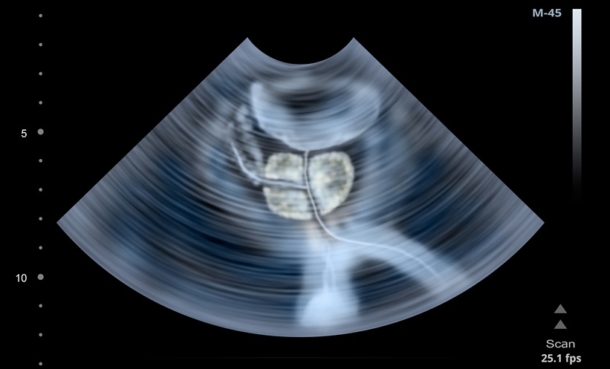

Immunohistochemical Biomarkers for Prognostic Stratification in Metastatic Prostate Cancer

New evidence shows PSA and Ki-67 tumour expression may help predict progression and guide treatment decisions in metastatic castration-sensitive prostate cancer.